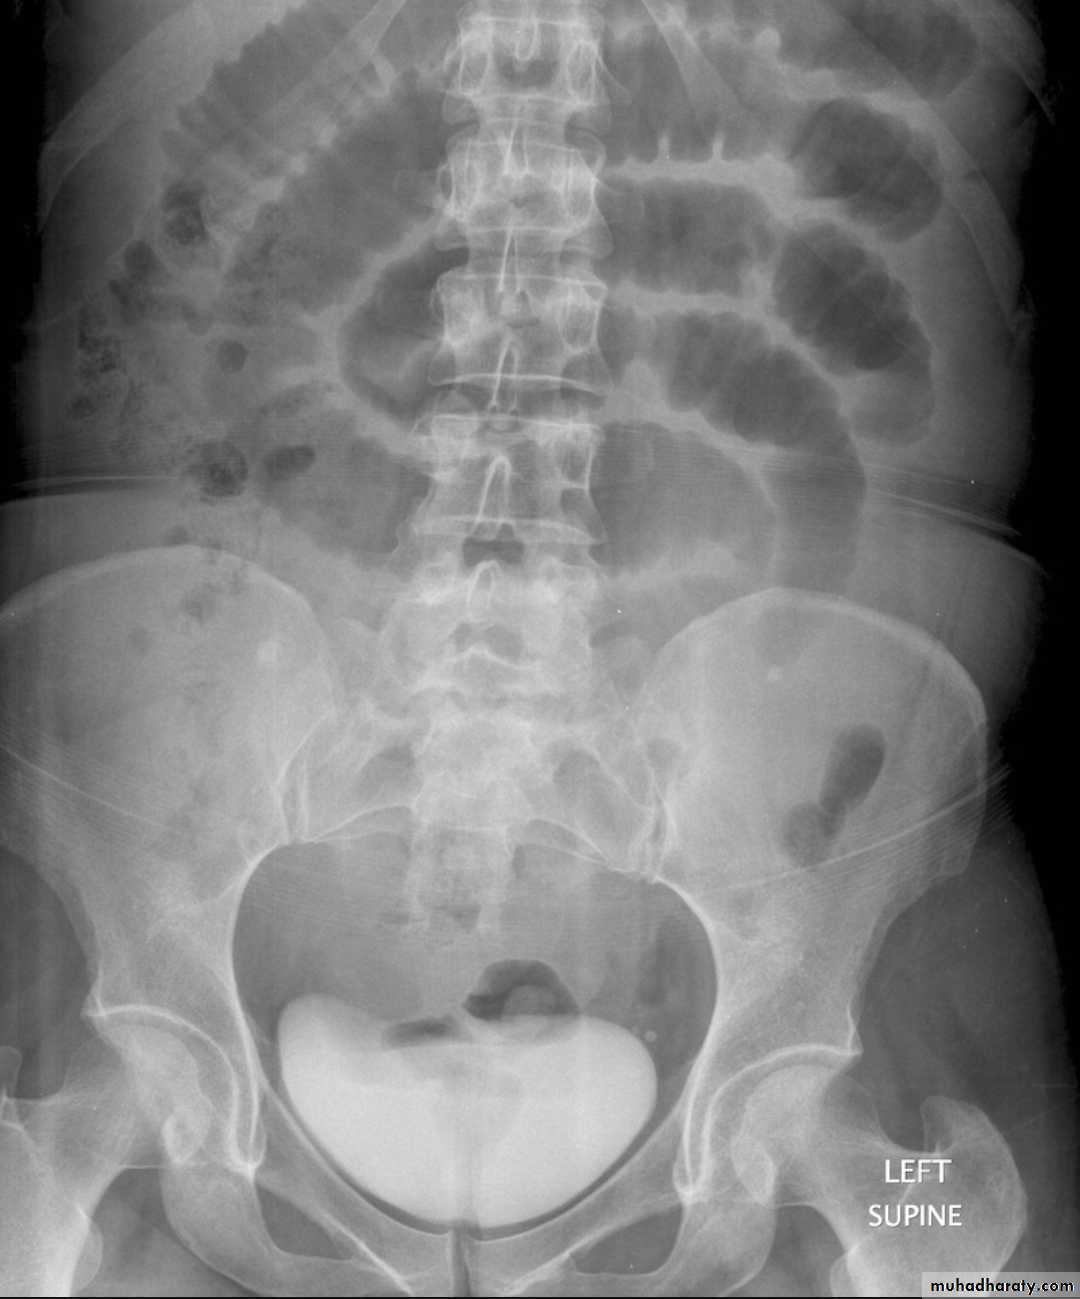

Large bowel obstruction (LBO) are often impressive on imaging, on account of the ability of the large bowel to massively distend. This condition requires prompt diagnosis and treatment

Radiographic features

Colonic distension > small bowel

Peripherally located

Dilated loops Less in no. than SBO

Presence of haustra